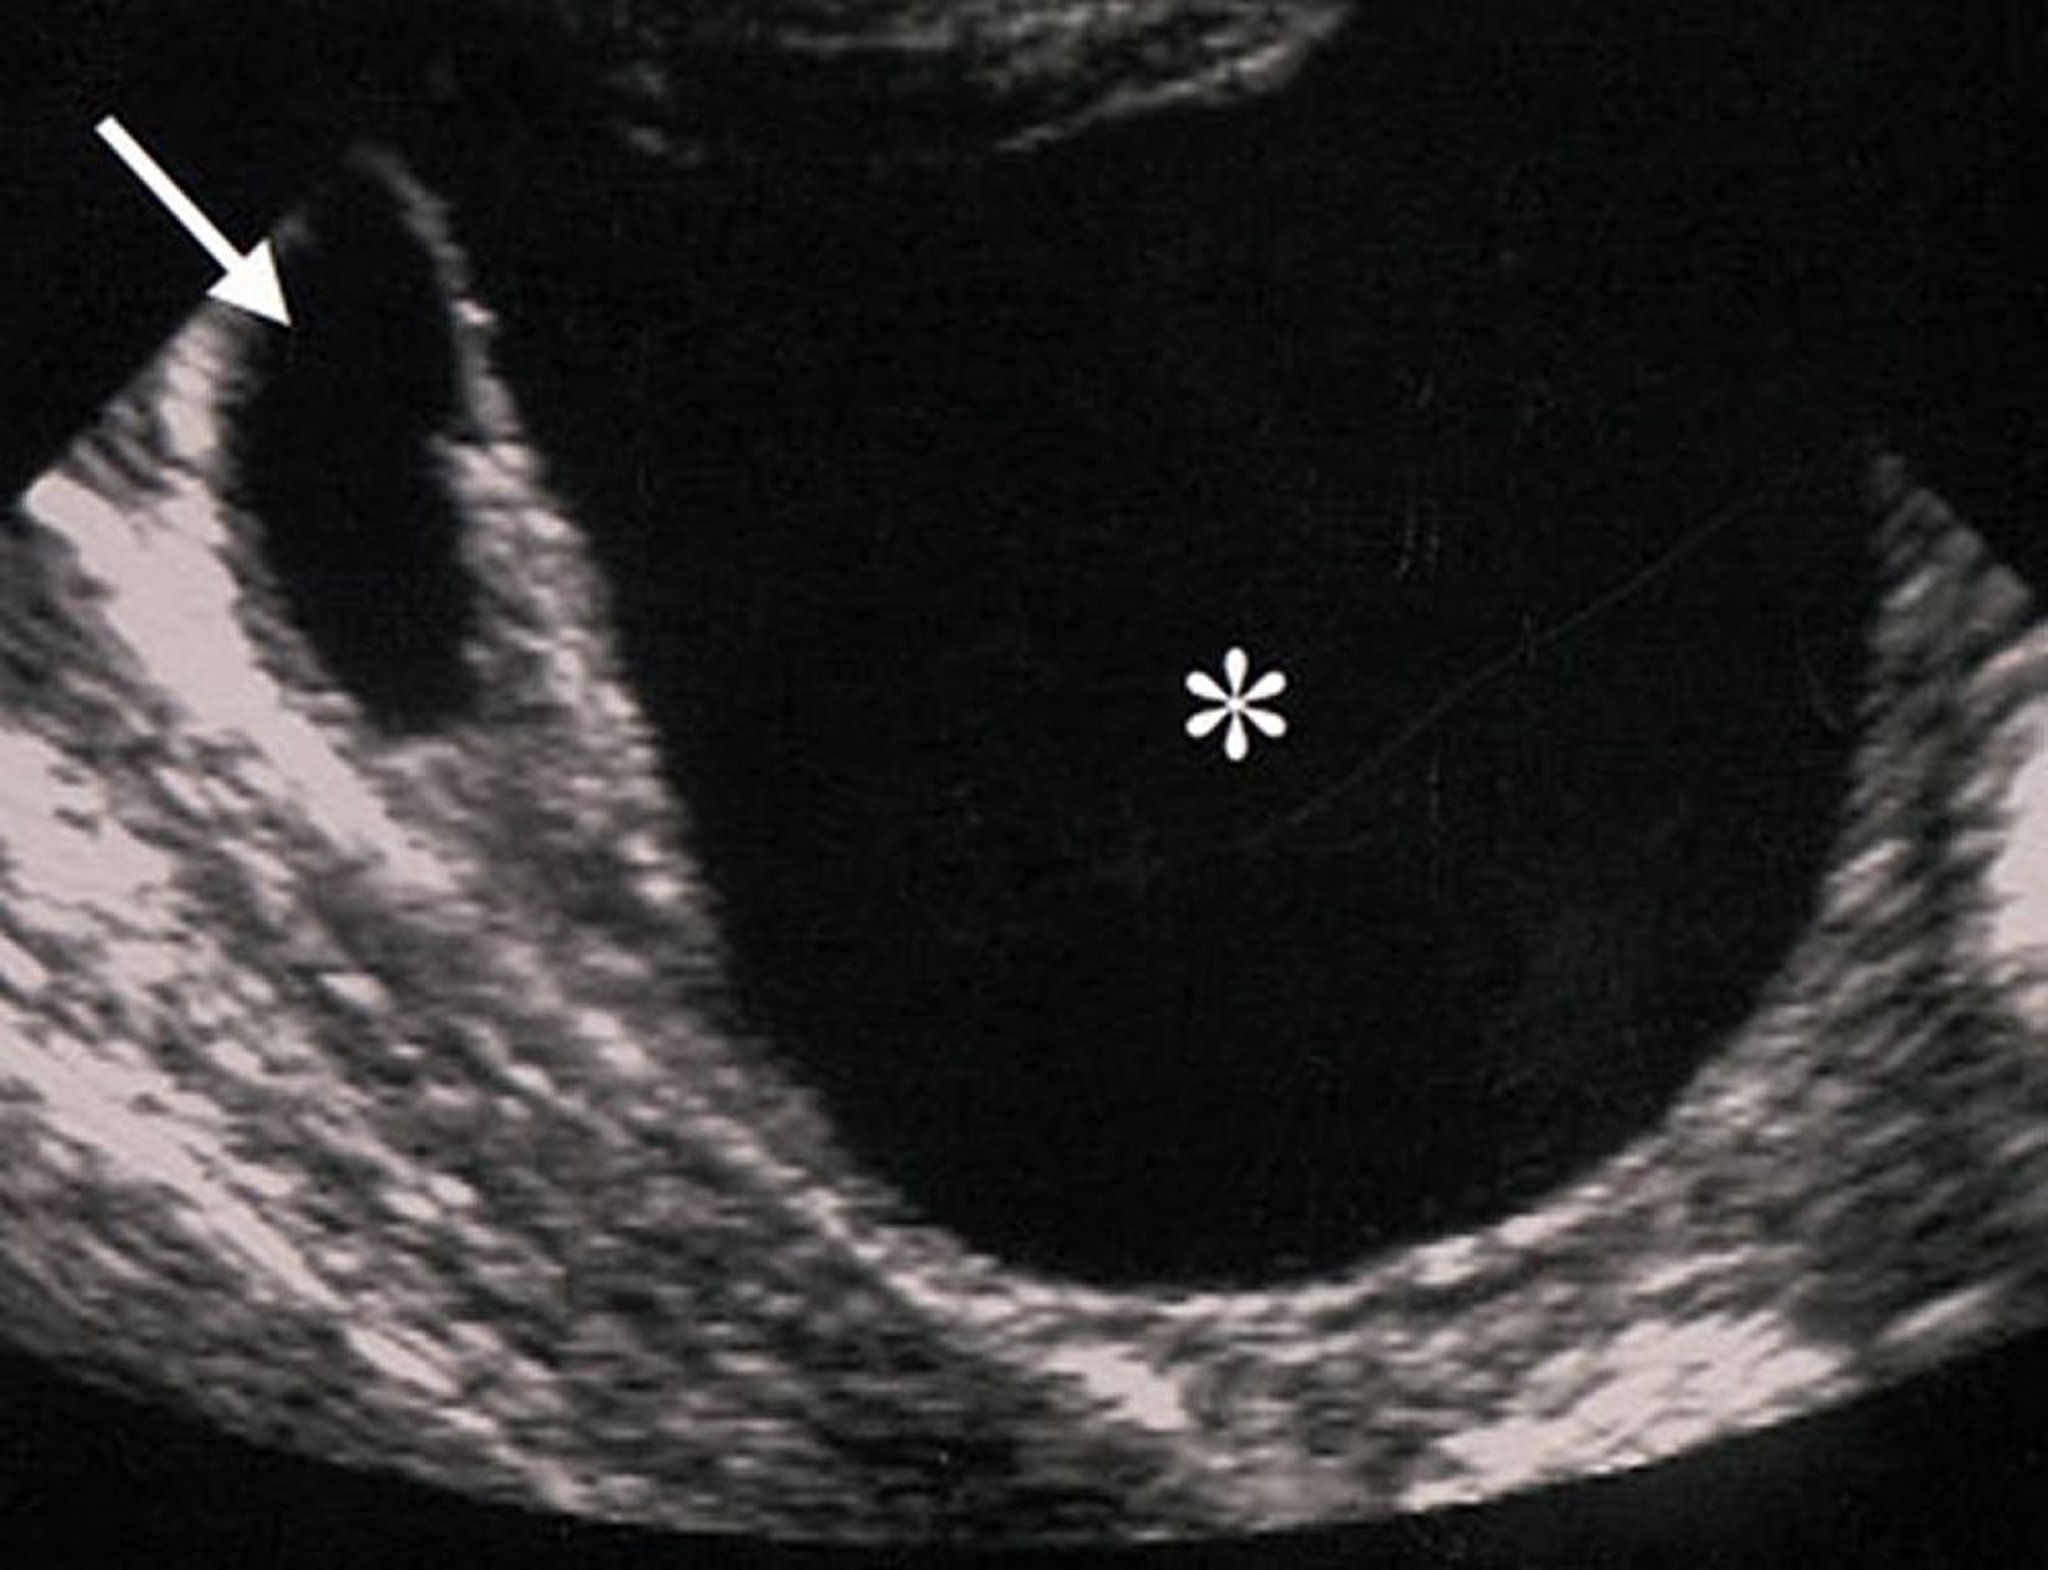

Ecografía de una masa ovárica benigna

Las características ecográficas de esta masa ovárica (indicada por un asterisco) sugieren que la masa es benigna. La masa es anecoica (lo que sugiere ausencia de componentes sólidos), regular, delímites netos y sin engrosamiento de la pared ni excrecencias.